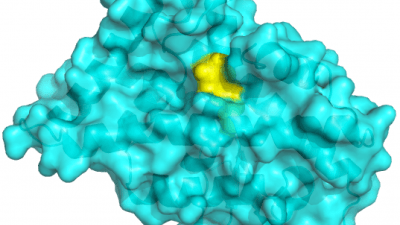

UCSF researchers developed a strategy for targeting a key molecule implicated in Parkinson’s disease, opening up a potential new treatment strategy for the currently incurable movement disorder.

Researchers discovered a scorpion toxin that targets the “wasabi receptor,” which they think it can be used as a tool for studying chronic pain and inflammation, and may eventually lead to the development of new kinds of non-opioid pain relievers.